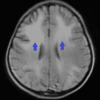

Figure 3. FLAIR image shows diffuse symmetrical, bilateral hyperintensities with preponderance of frontal lobes (blue arrows).

FLAIR: fluid-attenuated inversion recovery